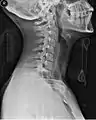

تظهر في الصورة فتاة في حالة طارئة وعليها طوق عنقي.

قد تسبب إصابات الرقبة كسوراً في العمود الفقري بالعنق ما يجعل المصابين على عرضة للإصابة الحبل الشوكي لديهم، وقد تتفاقم الإصابة مع حركة الشخص المصاب فيؤدي ذلك إلى الشلل أو الموت، ولذلك ولمنع حدوث المزيد من الضرر للمصابين بحوادث السيارات مثلاً يقوم المسعفون بوضع طوق حول أعناق المصابين في هذه الحوادث احترازياً حتى يتم التأكد عن طريق تصوير الأشعة السينية من عدم وجود كسر في هذه فقرات العنق السبعة. [1][2]